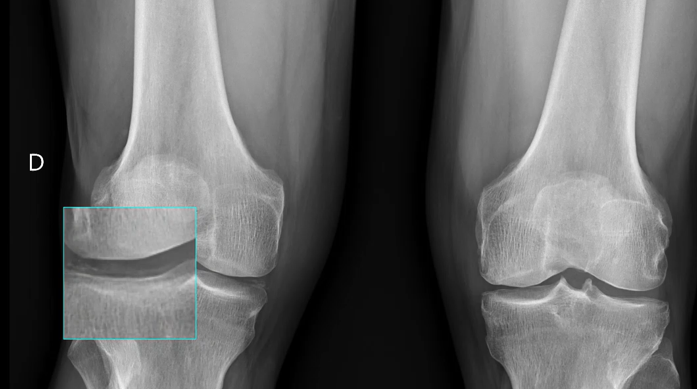

Radiografía: línea radiolucente paralela a la superficie tibial externa y en región meniscal medial. Sugestivo de condrocalcinosis.

Orientación diagnóstica. Por ecografía Patología meniscal (Condrocalcinosis) + por la exploración física Artrosis.